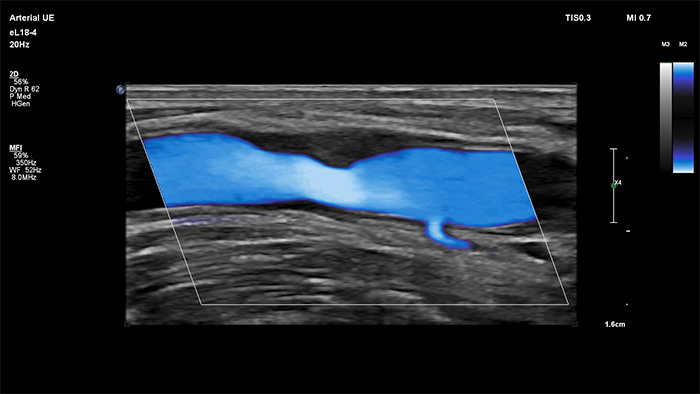

Philips MicroFlow Imaging wurde für die Erkennung langsamer und schwacher Blutflüsse in Gewebe entwickelt und verbessert bei Gefässuntersuchungen die Flussauflösung mit beeindruckender Empfindlichkeit. Subtile, pathologische Strömungsverhältnisse um stenotische Plaques lassen sich durch die hohe Auflösung und minimale Artefakte visualisieren und charakterisieren, was die Diagnosesicherheit unterstützt.